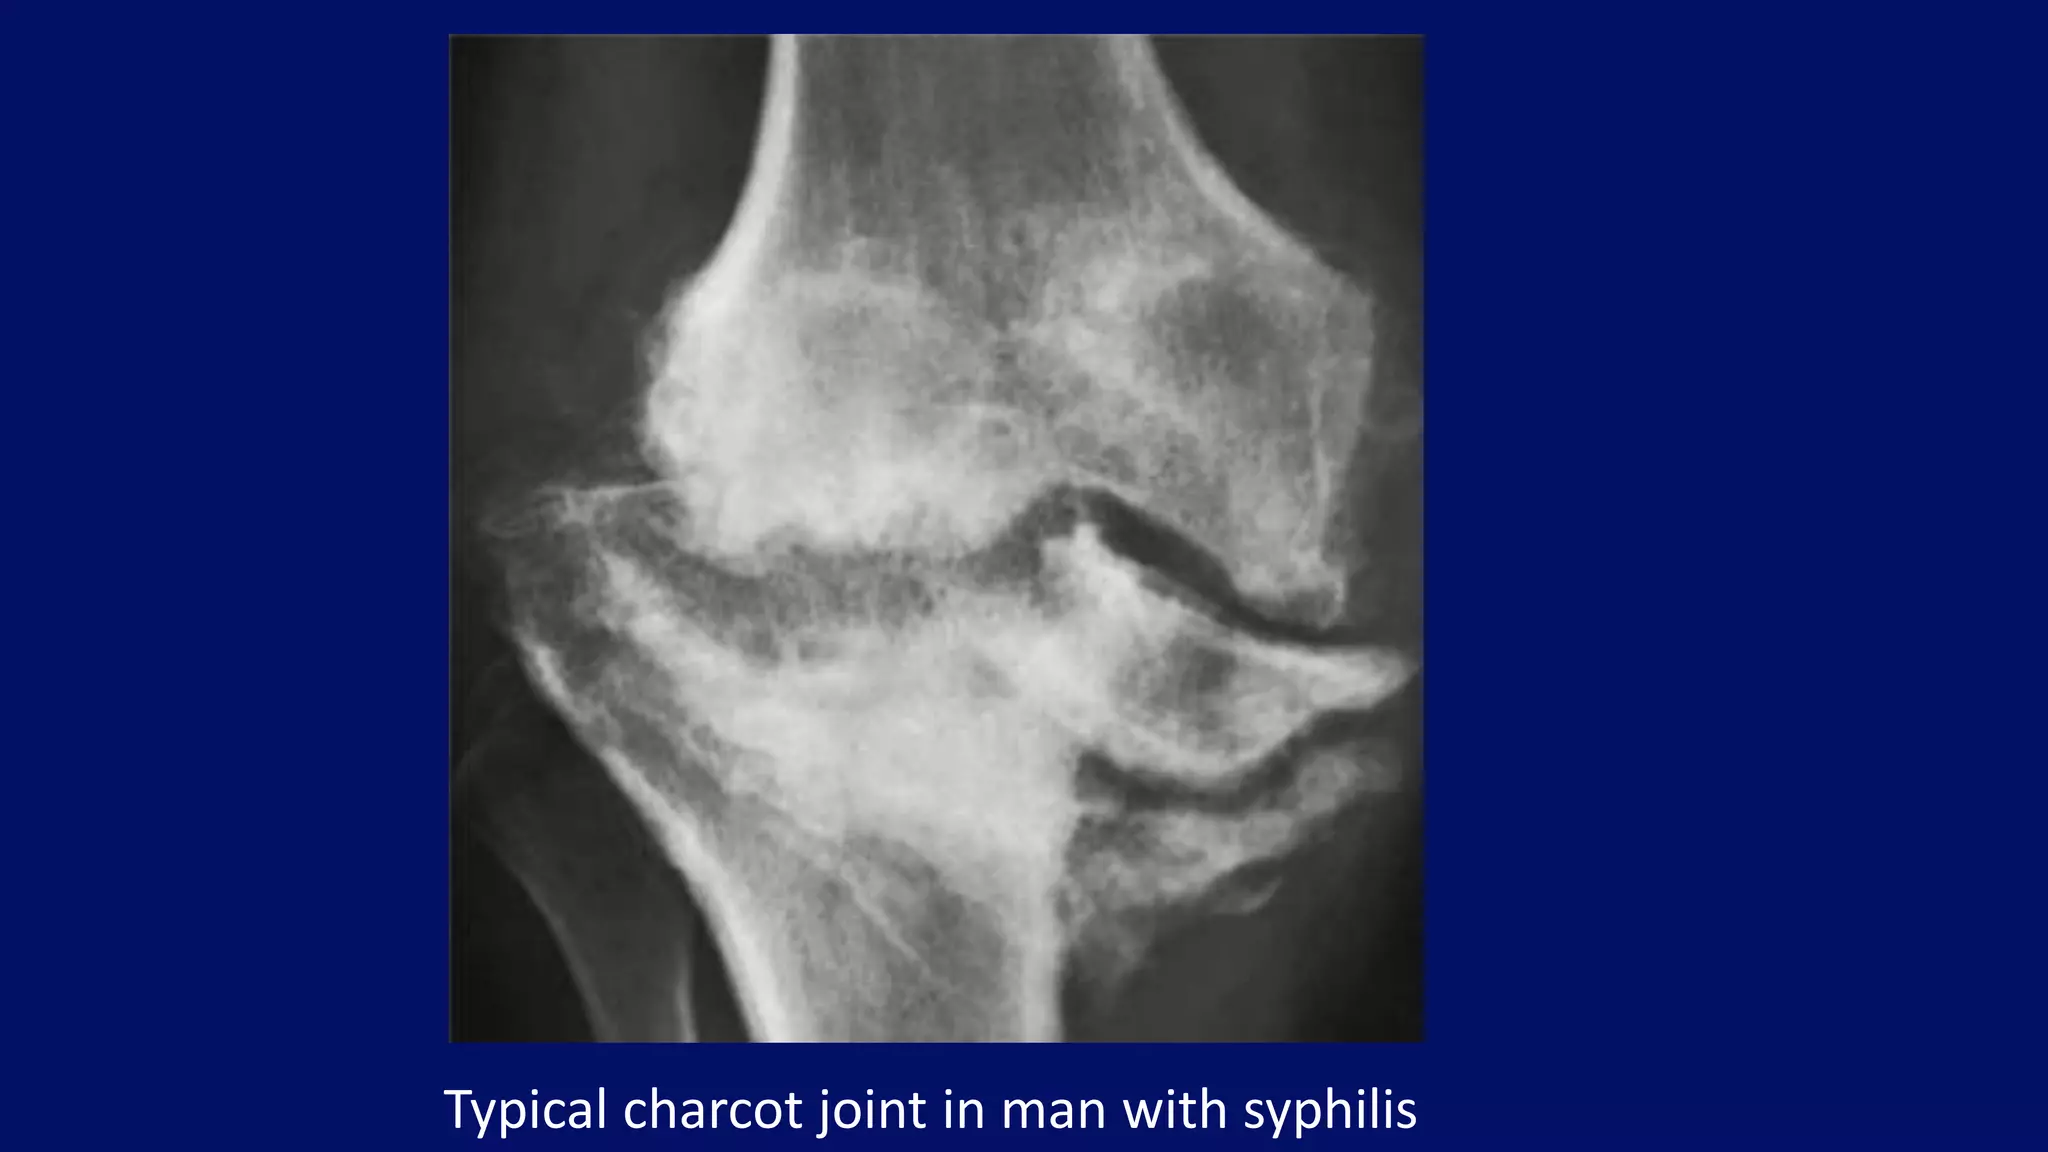

Typical charcot joint in man with syphilis

• #50 Neuropathic joint. Anteroposterior radiograph of the right hip of a 57-year-old woman with neurosyphilis (tabes dorsalis) shows the typical features of neuropathic (Charcot) joint. There is complete disorganization of the joint, fragmentation, and subluxation. The absence of osteoporosis is a characteristic feature of the neuropathic joint. This condition represents the most severe manifestation of degenerative joint disease.